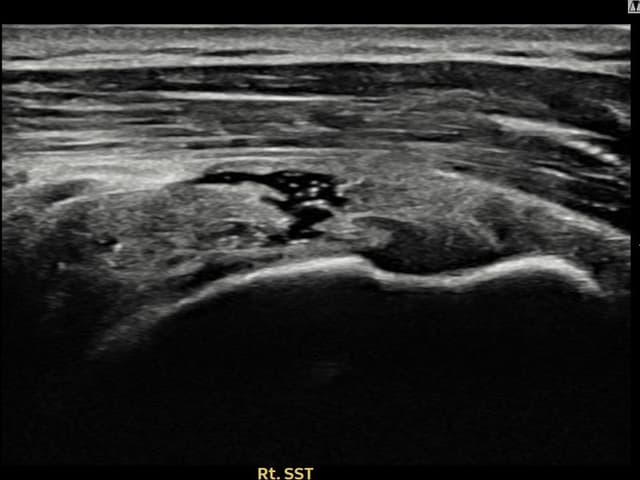

[촬영시기:21.09.27~21.10.07]

[석회분쇄흡입술] 우측 어깨의 야간 통증과 운동 제한으로 수개월간 고통받다 내원한 50세 남성 환자로, X-ray에서 극상근건 내 석회 침착이 확인되어 석회분쇄흡입술을 시행하였습니다.